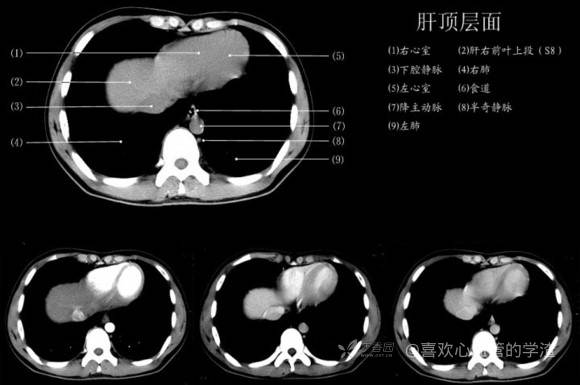

其实你离掌握上腹部 CT 影像只有一套高清实用图谱的距离,下面把我最喜欢的这本图谱分享给大家,为了方便阅读,我加了中文标识。后面附赠几张血管相对位置解剖关系图片,帮助大家理解(文中多图,建议在 wifi 环境下查看)。